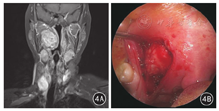

经口径路应严格掌握适应证,术前结合影像学等临床资料综合评估,对原发于咽旁间隙的良性肿瘤(除血管源性肿瘤),肿瘤突向口咽侧壁或软腭,边界清楚,位于颈动脉鞘内侧,与颈动脉鞘无明显粘连者,可考虑经口径路(图4)。对于茎突后间隙波及颈内动脉或需置换颈动脉的病变、波及茎突下颌管的唾液腺肿瘤、累及颅底骨质肿瘤以及副神经节瘤、体积过大的肿瘤等,不宜采用经口径路。在严格掌握手术适应证前提下,经口径路具有以下优点:路径短、视野清楚、创伤小,减少神经损伤和涎瘘风险,避免了面、颈部瘢痕、腮腺切除和咬合力下降等[36]。